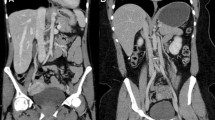

In this study evaluating the physical properties of UHRCT, we found that spatial resolution in SHR and HR modes is about twice as high as that of the MDCT at the isocentre. Spatial resolution away from the isocentre remains higher than the central resolution in MDCT, except at the outermost periphery. In Fig. 5, an example of separate abdominal scans of the same patient on MDCT and on UHRCT, using the HR mode, is shown. In this figure, it can be seen that the UHRCT acquisition results in a better delineation of structures.

Three axial venous phase contrast enhanced abdominal follow-up CT scans of a female patient with a resected stomach tumour at different time-points. (Left) MDCT at 100 kV with hybrid-iterative reconstruction (middle) UHRCT with HR mode at 120 kV with hybrid-iterative reconstruction and (right) UHRCT with HR mode at 120 kV with deep learning image reconstruction. Despite different contrast timing and tube potential compared with MDCT, the UHRCT using AIDR has better delineation of (retroperitoneal) structures, but more (fine grained) noise. Using deep learning image reconstruction with UHRCT results in even better delineation of the retroperitoneal structures and mesenteric vessels, with less perceived noise than in the other scans